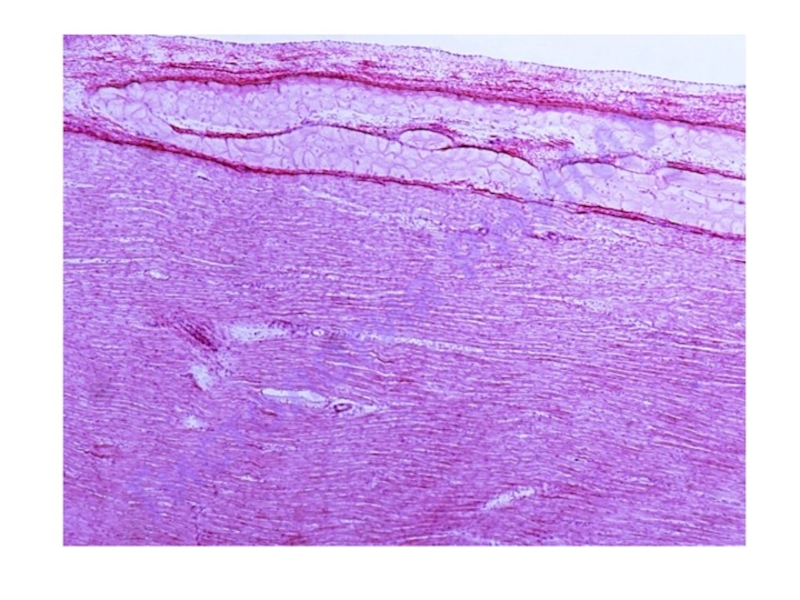

Слайд 12Наружная

эластическая мембрана

Наружная эластическая мембрана